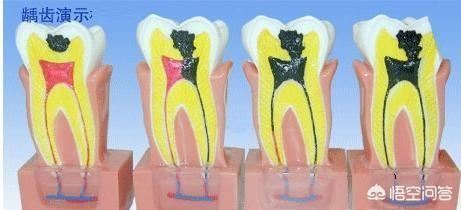

根尖周炎和牙槽脓肿大多先经历牙髓炎阶段。牙髓炎症未及时治疗容易发展至根尖周炎形成牙槽脓肿。

牙髓炎是牙髓受细菌感染后产生变性、分解由固态液化,如果此时牙髓腔还处于封闭状态由于液体的体积要大于固体因此在髓腔内产生压力压迫神经产生局部或放射性疼痛。(下颌牙发射至耳根一带,上颌牙放射至颞部太阳穴一带)。